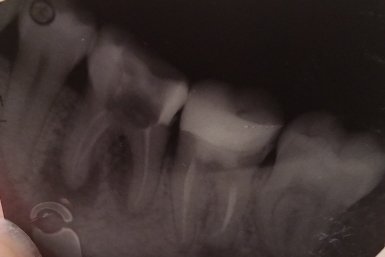

Из-за неправильного лечения образовалось воспаление под зубом и свищ сбоку на десне. В одной клинике сказали однозначно удалять, в другой, что есть 5% из 100, что можно как-то его спасти, но вряд ли.

Подскажите, пожалуйста, возможно ли вылечить зуб? Избавиться от гнойника вокруг него, чтобы не удалять зуб?

Однозначно зуб удаляется, нет там никаких пяти процентов успеха. Проблема связана, как с корнем зуба, так и по бифуркации.